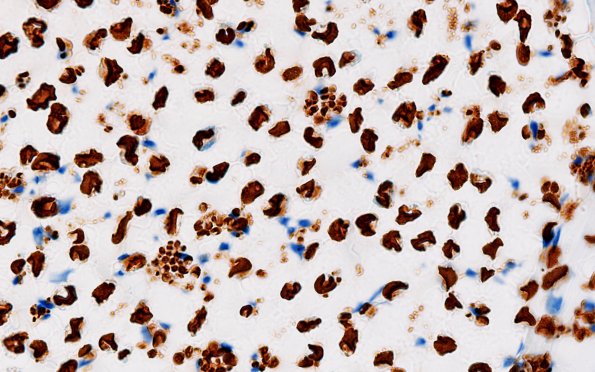

However, the axonal clusters are well demonstrated by neurofilament immunohistochemistry. The constituent axons are too large to represent Remak bundles. (NF IHC)